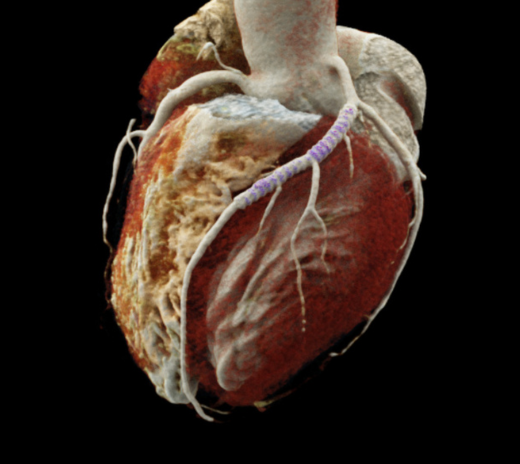

• 心脏科:冠状动脉影像清晰,即使严重血管钙化或置入支架仍可清晰显示。

超微细影像

能捕捉低至0.2毫米的精细影像切片,有助及早侦测微细病变。超高清影像特别适合冠状动脉血管植入支架的患者,能更准确评估细微结构及血管闭塞情况 。

冠状动脉血管